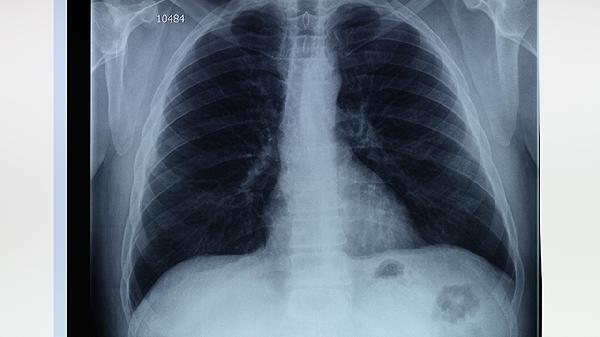

4、影像学特征:

通过CT检查可以观察到,肺气泡表现为散在的小点状透亮影,边界清晰。而肺大泡则呈现为单发或多发的无肺纹理透亮区,可能占据部分肺叶甚至整个肺叶。